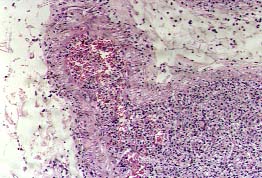

VI. CRIPTOCOCOSIS

La Criptococosis, cuyo organismo, el Cripotococcus neoformans, puede medir de 5 a 20 micras de diámetro y aparecen como espacios claros, que representan su cápsula no teñida. La respuesta del huésped es variable, dependiendo del estado de su inmunidad, de la enfermedad principal y de la encapsulación o no del hongo. Con frecuencia, la reacción celular es escasa o nula (Fig. 19); producen lagunas o "lesiones quísticas", en las que se ven formas muy pequeñas en gran cantidad (11). La presencia de levaduras gemantes las diferenciará de un artefacto. Las lesiones mas antiguas pueden ser granulomatosas, con o sin células gigantes y con necrosis caseosa.

19p.jpg (33797 bytes)

Fig. 19